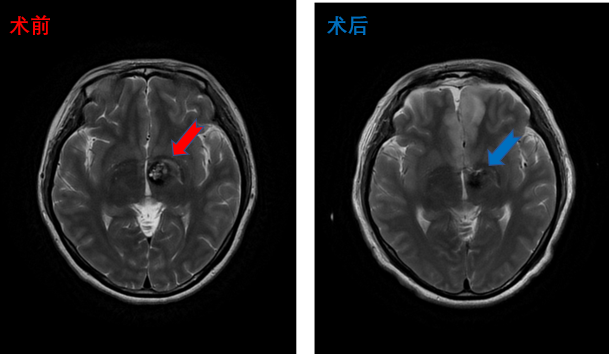

丘脑海绵状血管瘤患者影像,术后患者四肢活动正常

放射冠海绵状血管瘤患者影像,术后患者四肢活动正常